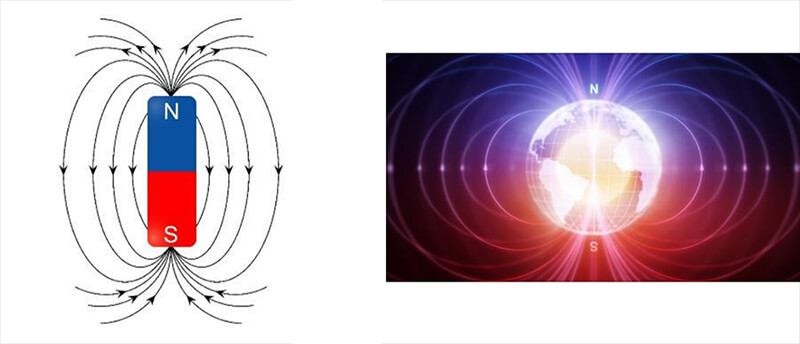

The imaging in MRI involves the very small magnetic force created by spinning protons within the nucleus of atoms. Protons are dipoles, much like the earth, with a north and South Pole and they spin or rotate on an axis. All dipoles process, or spin, at a unique frequency. This means that every proton has its own frequency at which it spins. This basic knowledge led to quite a realization about magnetic fields and signal given off by these magnetic fields under certain conditions, which we will learn more about as we progress. For now, it’s sufficient to say that this is the basis for what we know about MRI and how it works.

Before we go any further in that discussion, we need to understand a little more about the magnetic field. You may recall in grade school or later, playing with magnets in science class. These magnets would have been many millions of times LESS powerful than the magnet used in MRI. However, they all work with the same regardless of the strength. It is all the same physics concepts. This basic idea with magnetization is really the basis of MRI imaging. Let’s learn more about the magnetic field in MRI.

A magnetic field is defined as a region around a magnetic material or a moving electric charge within which the force of magnetism acts. Magnetism is an attraction and repulsion of forces between objects. This magnetism is observed around the earth. The earth is a larger scale example of a spinning object, which is also a dipole (north and south pole). The magnetic field of the earth allows us to use a compass to determine direction. We can also observe a magnetic field around permanent magnets and coils fed by electrical charge.

So, how do we create a magnetic field? If we place a permanent magnet on a surface coated with iron filings we can easily see the field lines on both sides of the magnet. Because of the ferrous properties of the iron filings, they are naturally attracted to the magnet. The Iron fillings with gather around and attach to the magnet within these field lines. Even if they do not all attach directly onto the magnet, they are within the magnetic field.